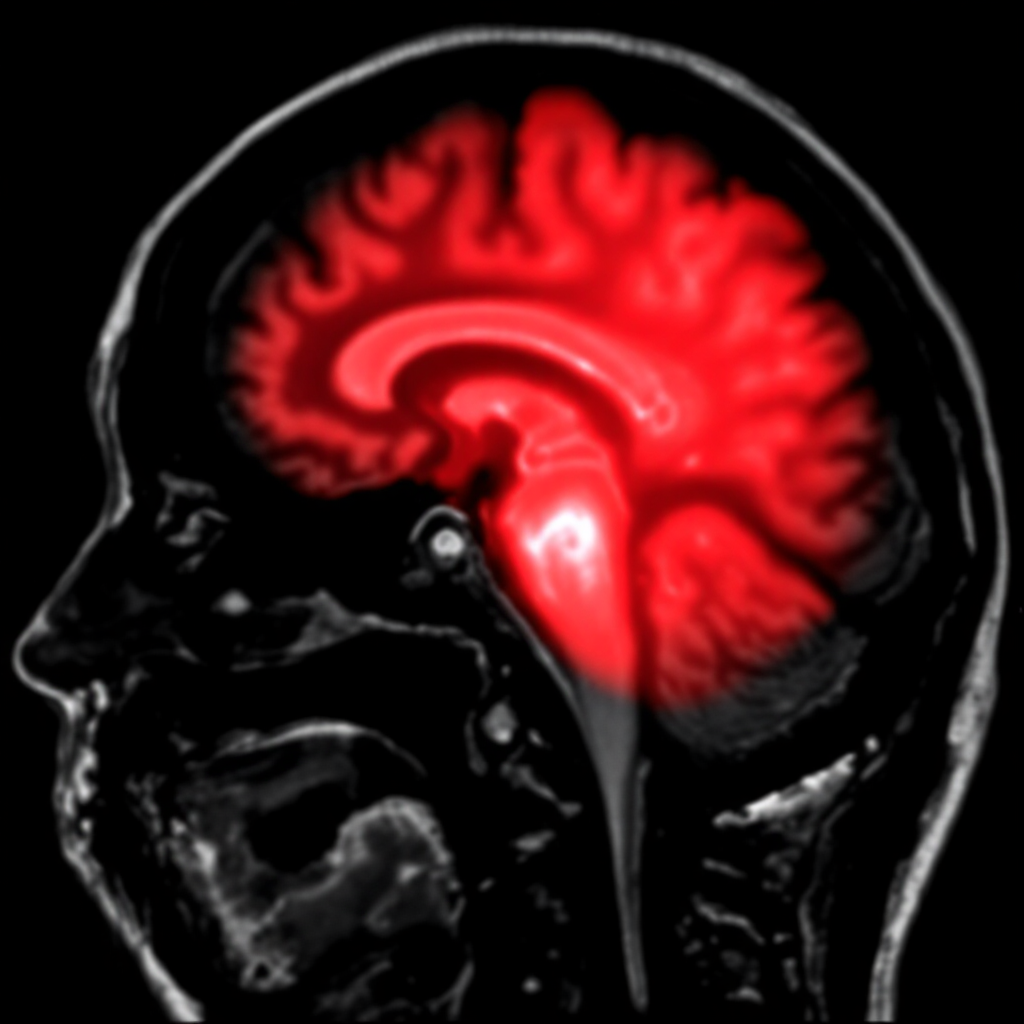

우측 뇌경색은 뇌의 우측 반구로 향하는 혈관이 막히거나 좁아져서 뇌 조직에 산소와 영양분 공급이 중단되는 상태를 말해요. 뇌는 좌우 두 개의 반구로 나뉘는데, 각각 다른 기능을 담당하고 있답니다. 우측 뇌는 주로 공간 지각, 시각적 처리, 감정 인식, 직관적 사고를 관장해요. 이 부위에 경색이 발생하면 좌측 신체 마비, 공간 무시 증후군, 감정 변화 등의 특징적인 증상이 나타나게 됩니다.

뇌 영상 검사는 뇌경색 진단에서 가장 중요한 검사예요. CT(컴퓨터 단층촬영)는 가장 먼저 시행하는 검사로, 뇌출혈을 배제하고 뇌경색의 초기 변화를 확인할 수 있어요. 하지만 CT는 발병 초기에는 뇌경색 병변이 잘 보이지 않는 경우가 많아서 MRI(자기공명영상)를 추가로 시행하게 됩니다. MRI의 확산강조영상(DWI)은 뇌경색 발생 후 수분 내에도 병변을 정확하게 찾아낼 수 있어서 조기 진단에 매우 유용해요.